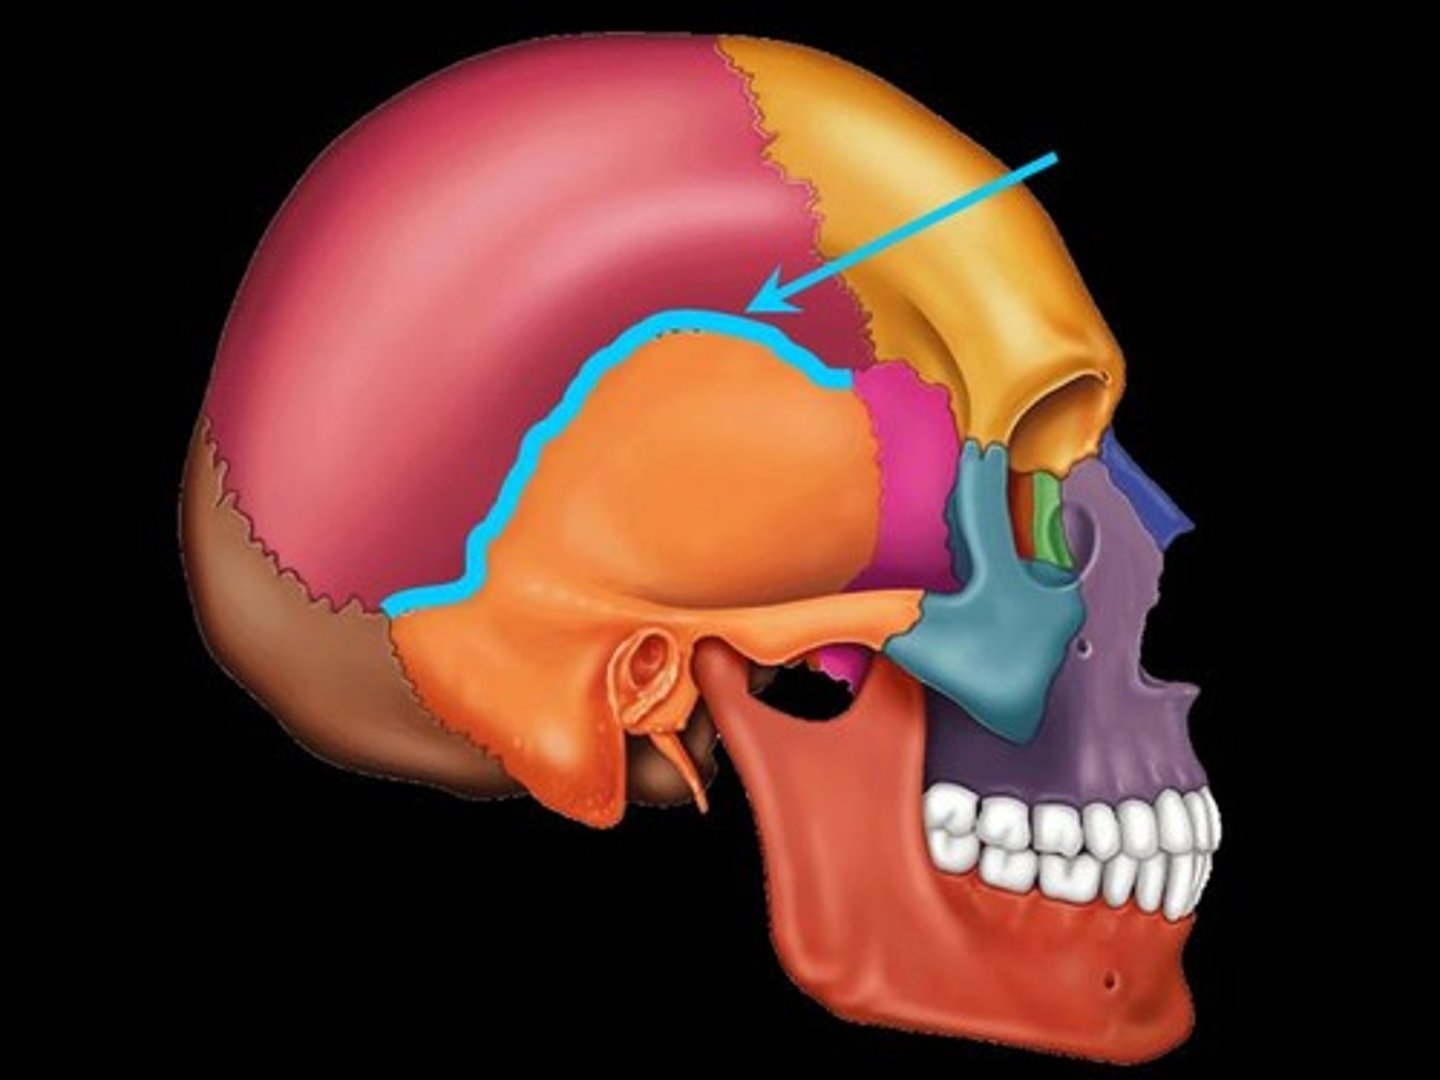

squamosal suture

lambdoidal suture

pterion

asterion

parietal bone

sphenoid bone

temporal bone